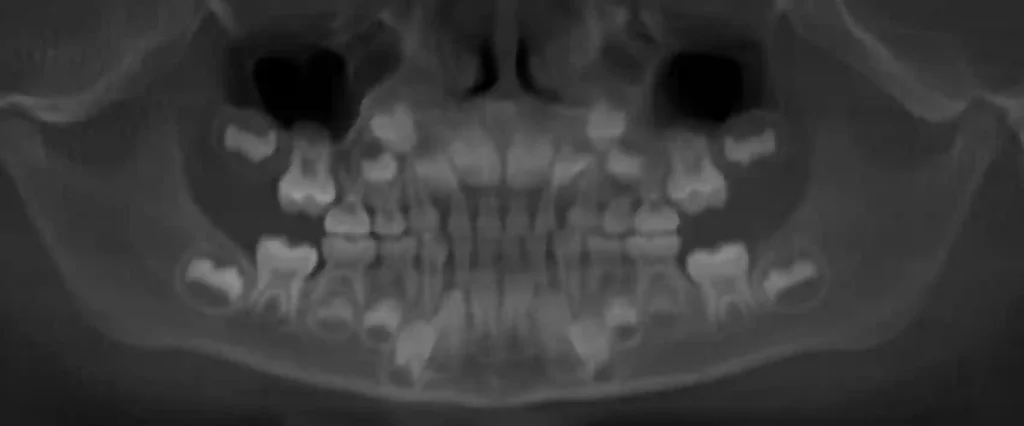

ترتیب افتادن دندان‌های شیری در کودکان

جدول کامل زمان‌بندی افتادن دندان‌های شیری

نوع دندانسن تقریبی افتادن

دندان پیشین پایین۶ تا ۷ سال

دندان پیشین بالا۷ تا ۸ سال

دندان‌های کناری جلو۸ تا ۹ سال

آسیای اول شیری۹ تا ۱۰ سال

نیش شیری۱۰ تا ۱۲ سال

آسیای دوم شیری۱۰ تا ۱۲ سال

📌 روند کامل جایگزینی دندان‌های شیری معمولاً تا ۱۲ سالگی تکمیل می‌شود.

نمودار ترتیب افتادن دندان شیری

6-7 سال  → دندان جلو پایین

7-8 سال → دندان جلو بالا

8-9 سال → دندان‌های کناری

9-11 سال → دندان‌های آسیای شیری

10-12 سال → دندان‌های نیش و آسیای دوم